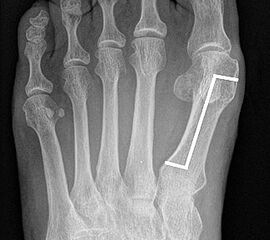

Die Röntgenaufnahmen (Abbildung 1) zeigen den Fuß einer 34 jährigen Patientin nach Exostosenabtragung. Der erhöhte intermetatarsale Winkel wurde durch eine alleinige Abtragung der Exostose nicht reduziert. Als weiterer Risikofaktor für ein Rezidiv liegt ein pathologischer Gelenkwinkel vor. Der intermetatarsale Winkel von 18 Grad kann durch eine basisnahe Osteotomie gut korrigiert werden. Da durch die gleichzeitige distale Korrektur des Gelenkflächenwinkels mithilfe einer Reverden-Green Osteotomie ein Längenverlust von ca. 2-4 mm einhergeht, bot sich als proximales Korrekturverfahren die basisnahe Open-wedge Osteotomie an, um bezüglich der Länge des Metatarsale I neutral zu bleiben (Abbildung 2). Die Kombination zweier verkürzender Verfahren (z.B. Lapidus und Reverden-Green) würden zu einem sehr kurzen ersten Strahl führen, mit dem Risiko einer Transfermetatarsalgie. Übersteigt die Verkürzung des Metatarsale I 2 mm, steigt das Risiko für die Entwicklung einer Transfermetatarsalgie deutlich an 8. Die durchgeführte Revision zeigt eine gute Stellung des 1. Strahls bei zentriert stehendem Gelenk.